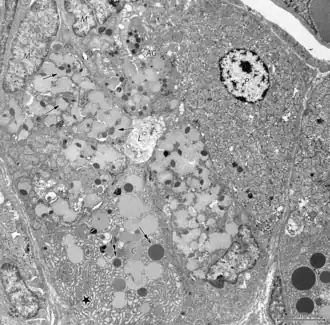

Ultraestructura

Con el microscopio electrónico se han podido describir, ubicar y sistematizar las células que integran las glándulas gástricas.[7][2]